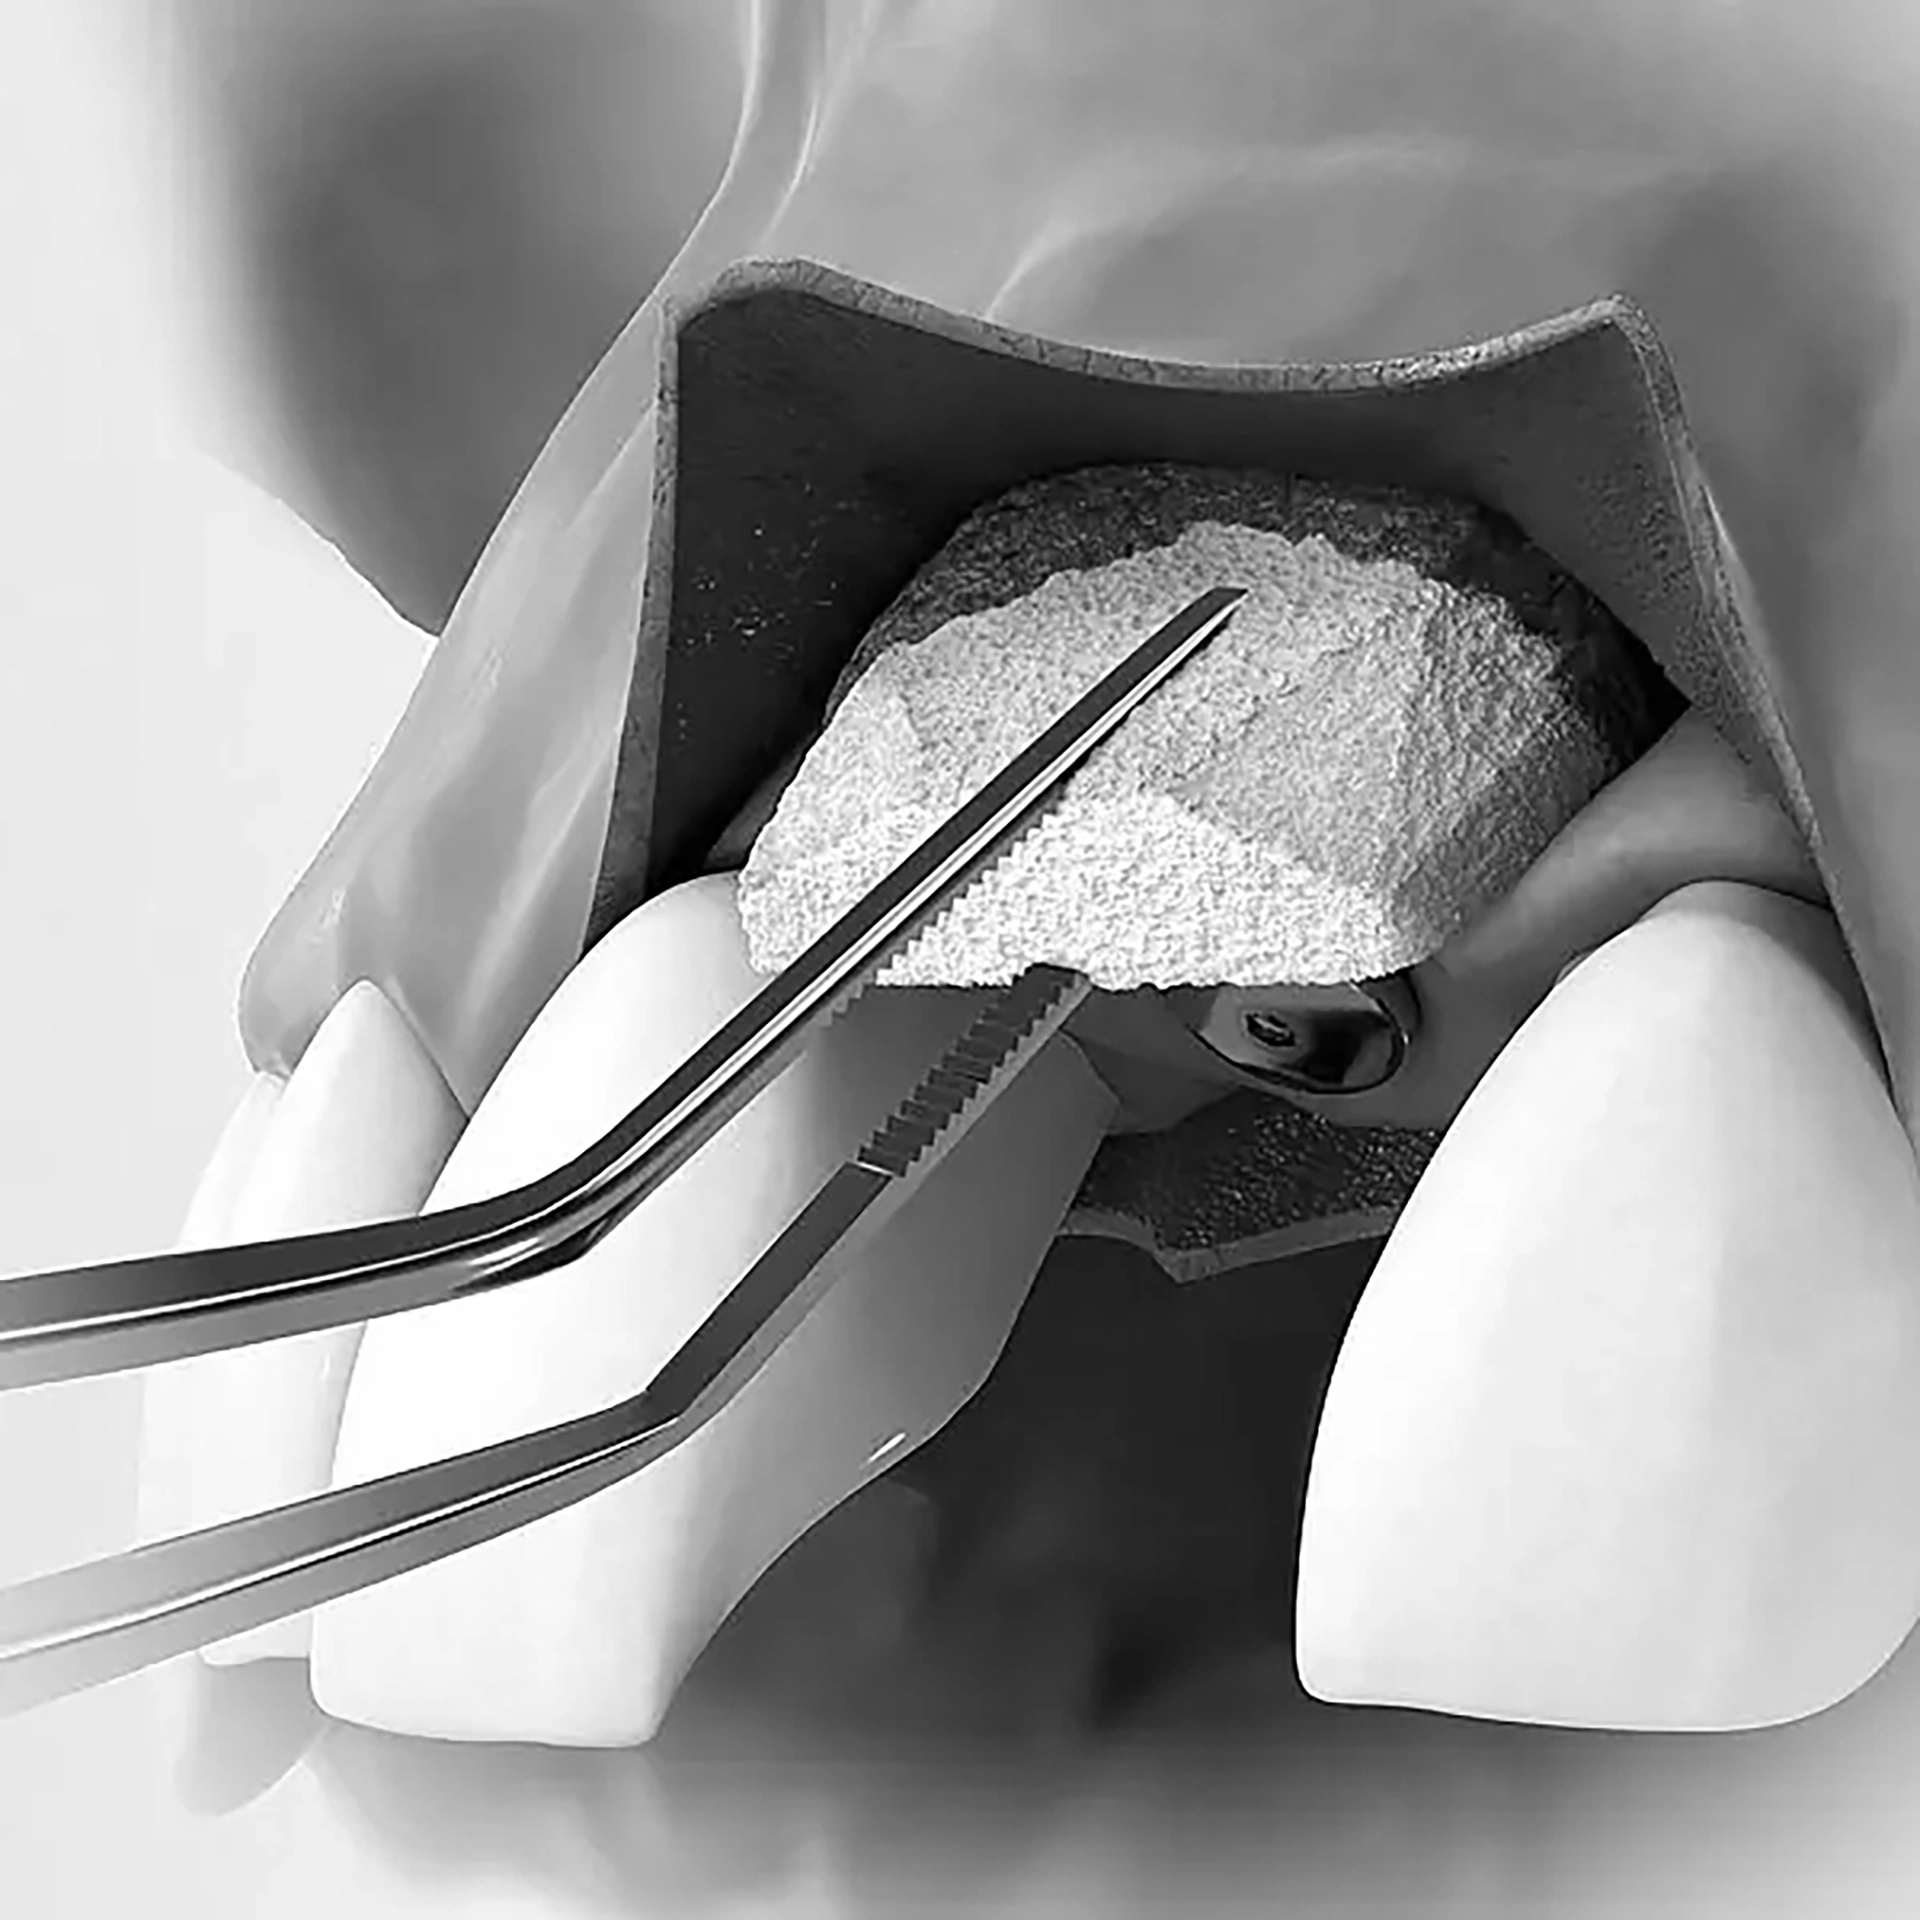

Hard Tissue Augmentation

Restores lost bone in areas where dental implants are planned. Bone grafts—either natural or synthetic—are used to rebuild the alveolar bone for strength and stability

Hard tissue augmentation 3 (c)

Soft Tissue Augmentation

Enhances gum volume and contour for natural aesthetics and support around implants or areas of gum recession.

Graft materials may be sourced from your tissue, synthetic alternatives, or animal-derived grafts to achieve the best results.